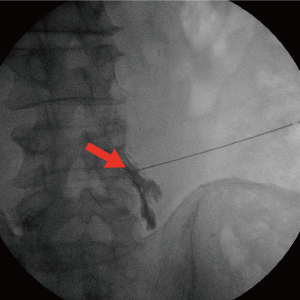

Treatment until the last painC-arm(특수영상치료장치)을 보며 치료하는 척추 비수술치료로 척추의 신경을 둘러싸고 있는 경막 바깥쪽에 약물을 투입하는 시술입니다. 허리 또는 목의 손상된 척추 부위에 가는 바늘을 통해 직접적으로 약물을 투입함으로써 신경 주위 염증과 부종을 가라 앉히며, 자율신경계의 정상적인 반응을 유도하는 치료입니다.

국소마취 하 디스크와 신경 사이에 정확히 바늘을 삽입하여 신경을 안정시키고 염증을 완화시킵니다.